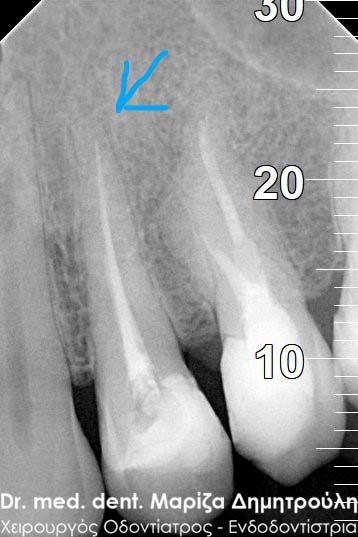

Η ασθενής προσήλθε με έντονο πόνο στο ιατρείο και είχε λάβει τις προηγούμενες μέρες αντιβίωση, εφόσον στην άνω αριστερή πλευρά της είχε οίδημα. Μετά την κλινική εξέταση διαπιστώθηκε η ύπαρξη ενός συριγγίου υπερώια μεταξύ των δύο άνω αριστερών γομφίων. Πραγματοποιήθηκε ακτινογραφία με την τοποθέτηση ενός κώνου γουταπέρκας για τη διάγνωση του υπαίτιου δοντιού, που είχε προκαλέσει την εμφάνιση του συριγγίου. Σύμφωνα με όσα αποκάλυψαν η κλινική και ακτινογραφική εξέταση ακολούθησε η έναρξη απονεύρωσης στο δεύτερο άνω αριστερό γομφίο, δεδομένου οτι είχε ένα βαθύ λευκό σφράγισμα ρητίνης που εκτεινόταν στο ύψος του νεύρου του δοντιού. Το δόντι είχε έντονα συμπτώματα πόνου κατά την επίκρουσή του.

Μετά την ολοκλήρωση της απονεύρωσης στο δεύτερο άνω αριστερό γομφίο το δόντι είναι ασυμπτωματικό. Η αποκατάσταση του δοντιού πραγματοποιήθηκε με λευκό σφράγισμα ρητίνης, εφόσον το έλλειμμα των οδοντικών ιστών ήταν μικρό και δε χρειαζόταν η προστασία του δοντιού με θήκη / στεφάνη δοντιού.

Σε δεύτερη φάση θα ακολουθήσει η επανάληψη απονεύρωσης στον πρώτο άνω αριστερό γομφίο, καθώς η απονεύρωση του δεν καλύπτει όλο το μήκος των ριζών του δοντιού και το δόντι μετά το πέρας της ενδοδοντικής θεραπείας συνεχίζει να πονά.

ΠΡΙΝ